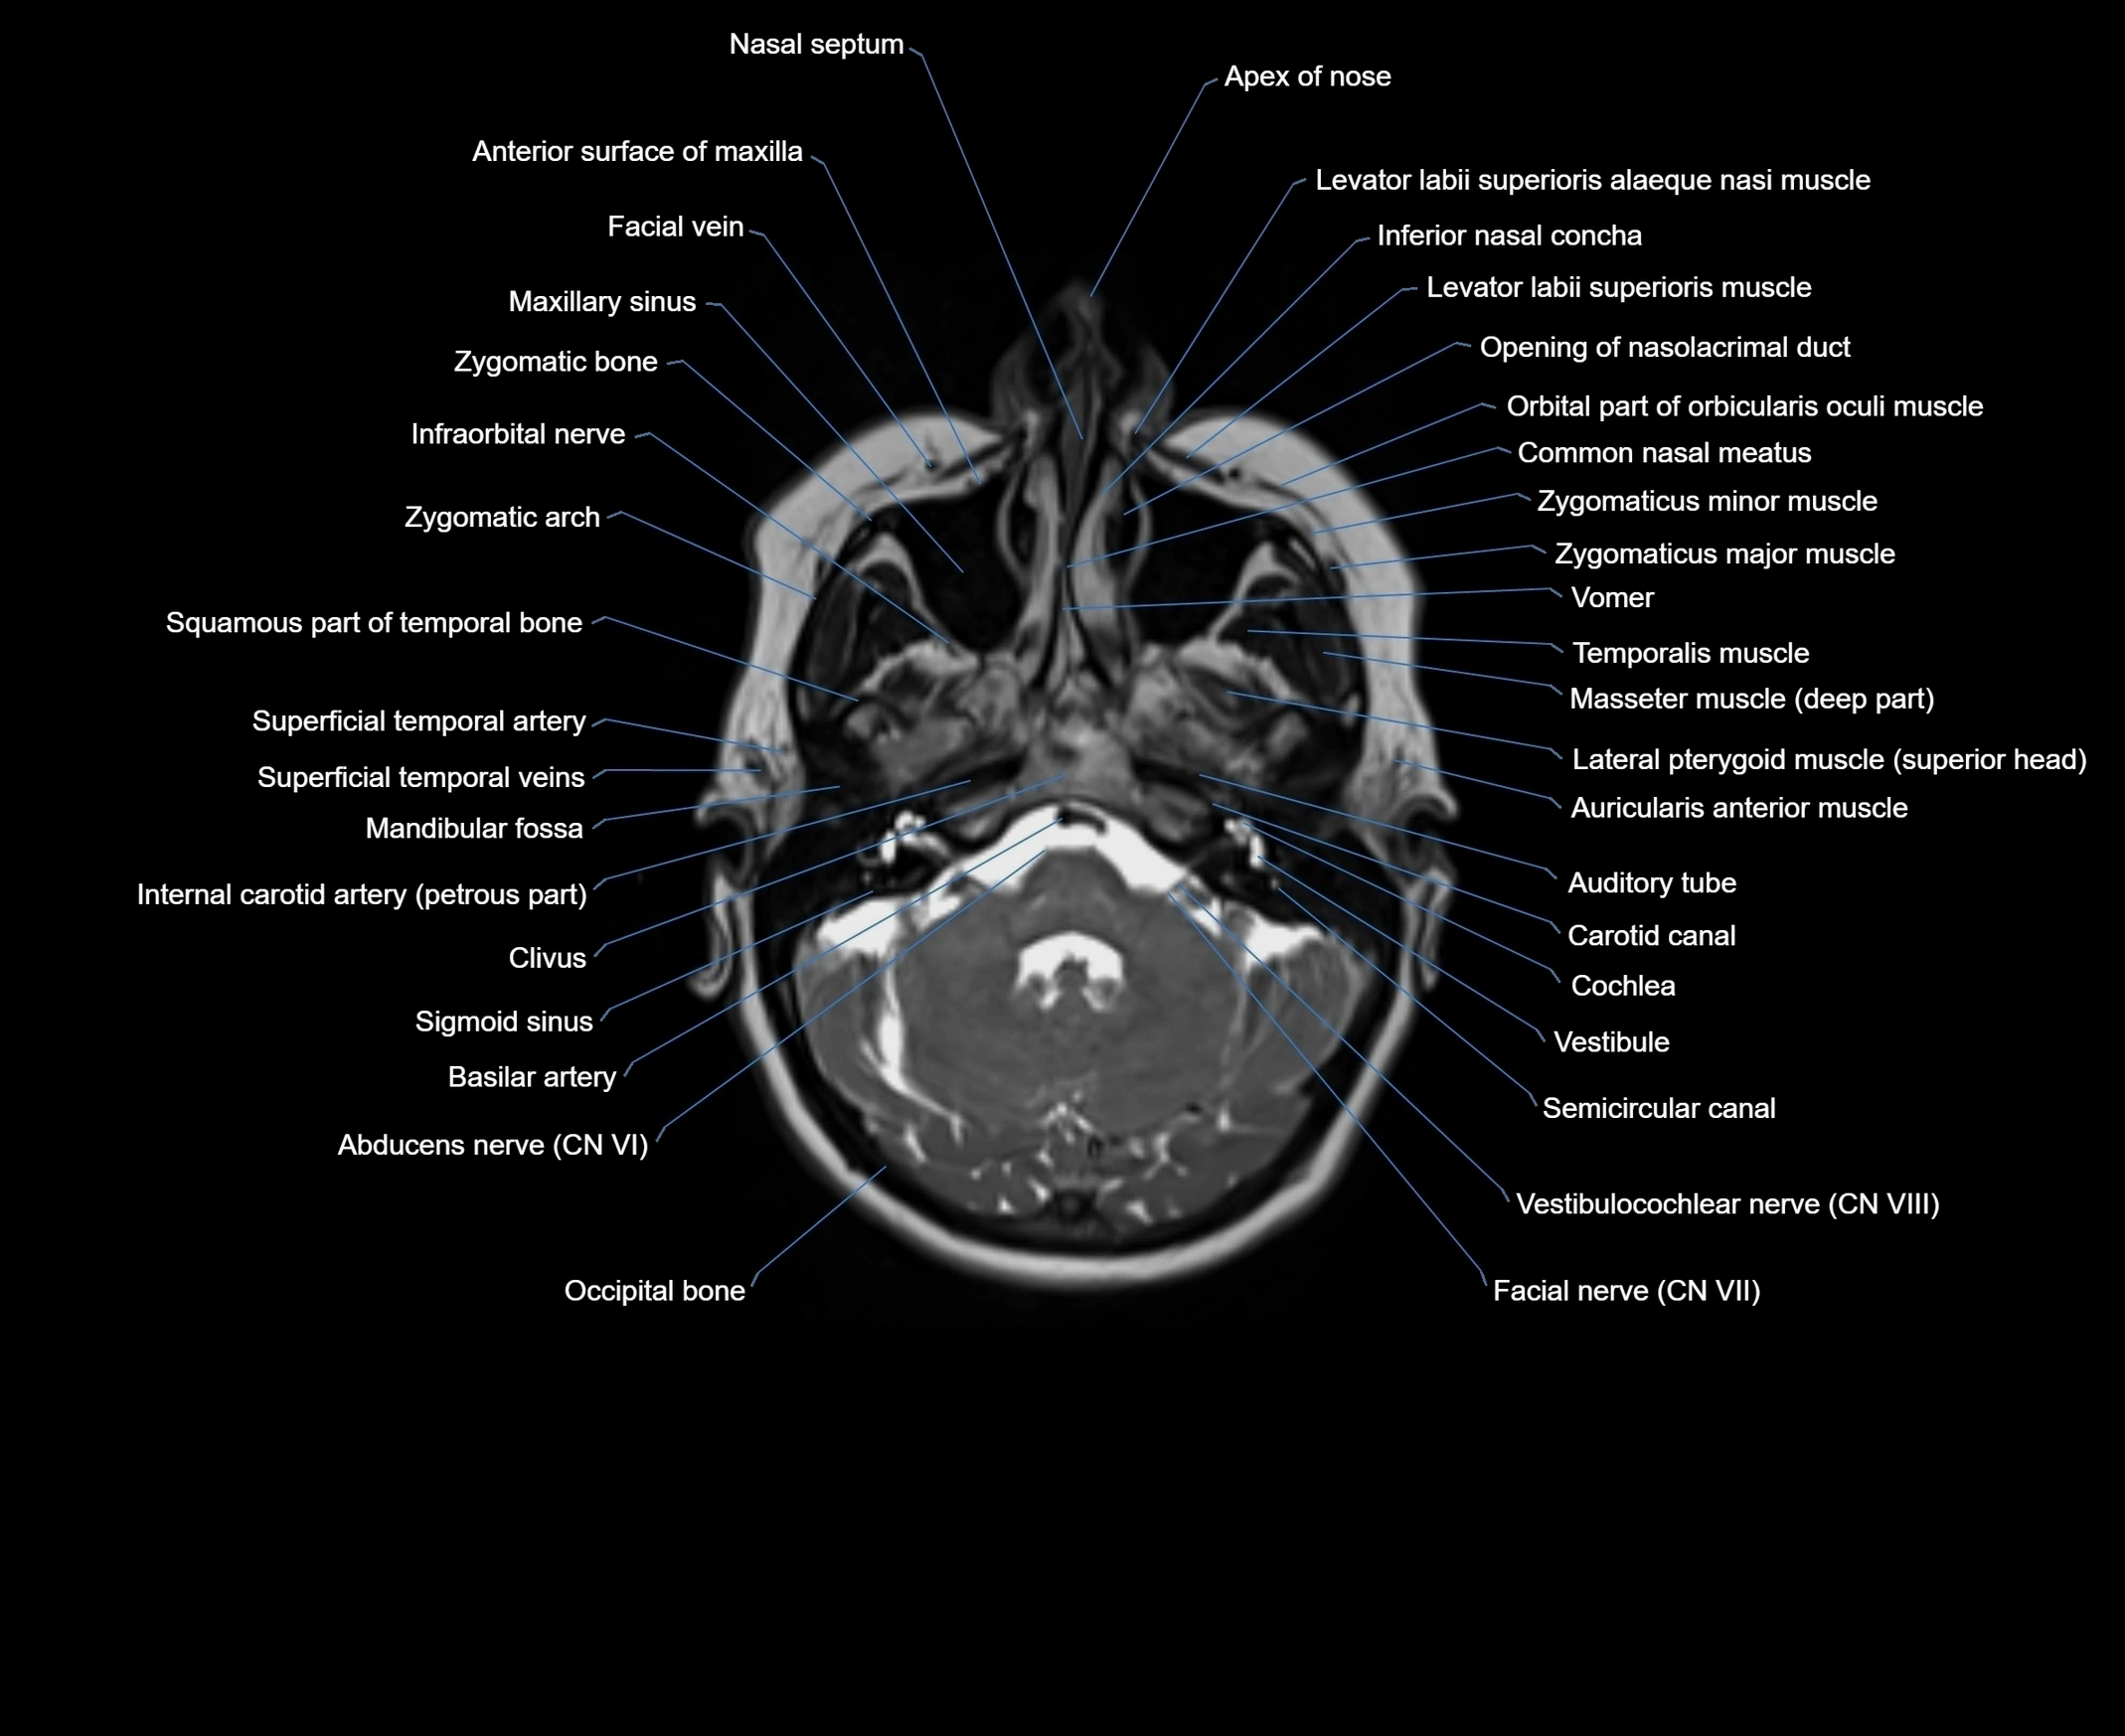

- Abducens nerve (Cranial nerve VI)

- Carotid canal

- Cerebellum

- Cochlea

- Common nasal meatus

- Facial Nerve (Cranial nerve VII)

- Facial vein

- Infraorbital nerve

- Internal carotid artery (petrous part)

- Levator labii superioris alaeque nasi muscle

- Levator labii superioris muscle

- Mandibular fossa

- Maxillary sinus

- Occipital bone

- Opening of nasolacrimal duct

- Orbicularis oculi muscle

- Orbital part of orbicularis oculi muscle

- Semicircular Canals

- Squamous part of temporal bone

- Superficial temporal artery

- Superficial temporal vein

- Temporalis muscle

- Vestibule

- Vestibulocochlear nerve (Cranial nerve VIII)

- Vomer

- Zygomatic arch

- Zygomatic bone

- Zygomaticus major muscle

- Zygomaticus minor muscle